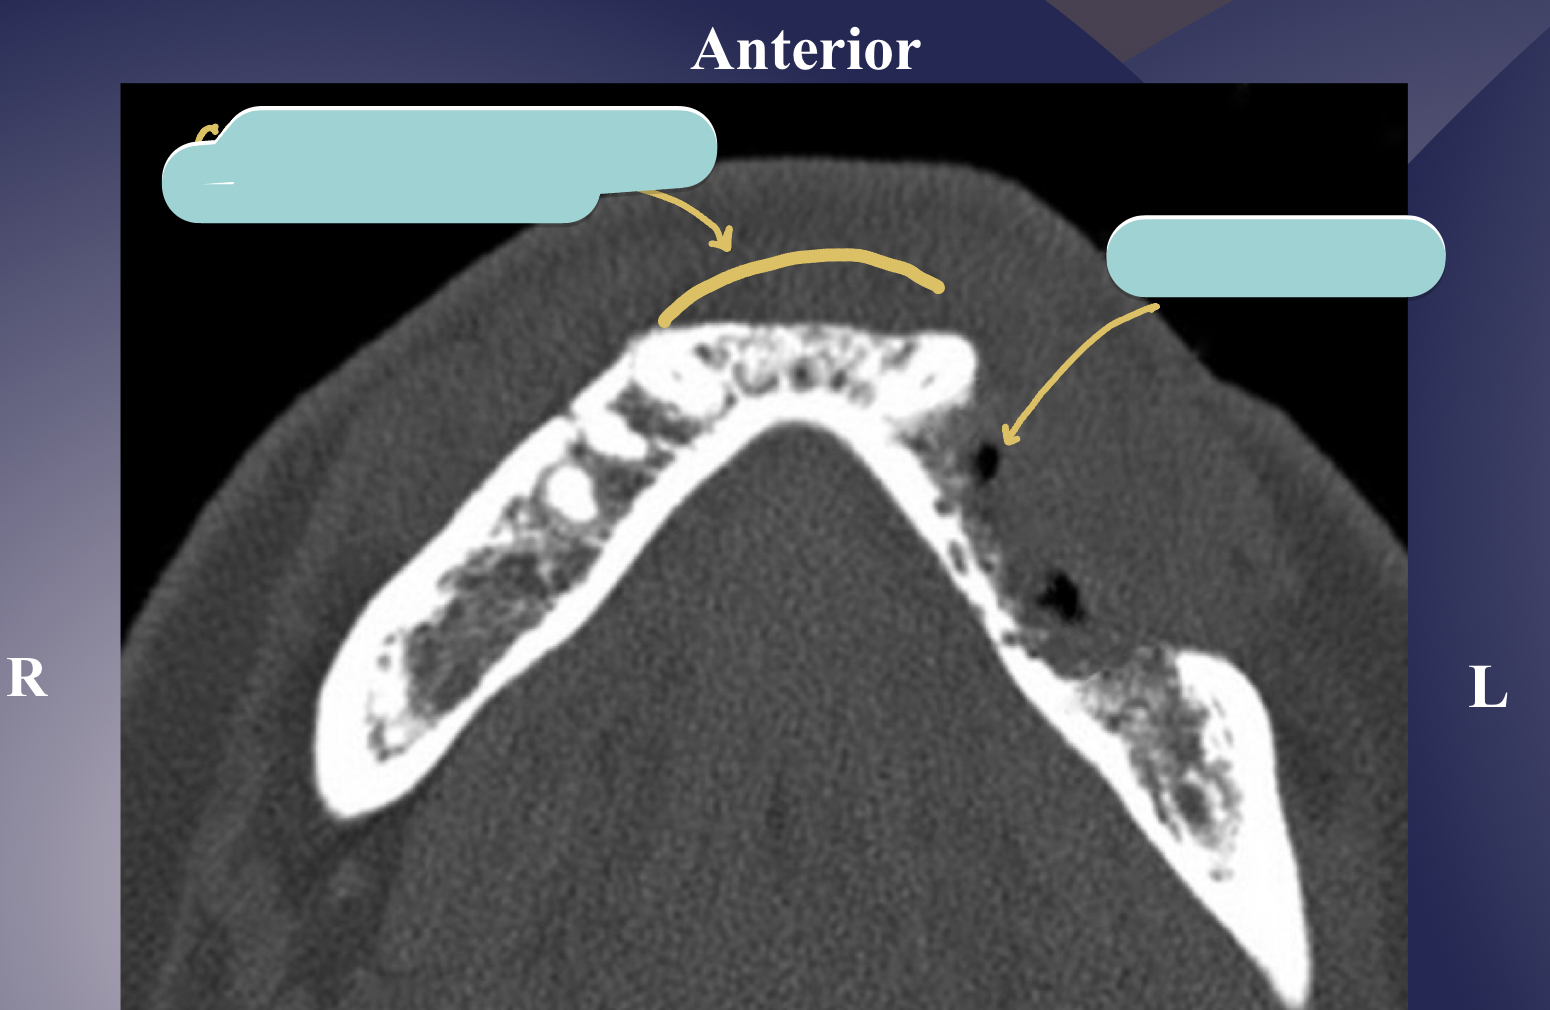

CT/CBCT

which type of chronic osteomyelitis?

primary response: proliferation reaction

sclerotic appearance of involved bone

subperiosteal bone deposition

slight jaw enlargement

involves large segment of jaw

diffuse sclerosing osteomyelitis

diffuse sclerosing osteomyelitis, young pt

diffuse sclerosing of left angle-ramus of mandible = L more radiopaque than R